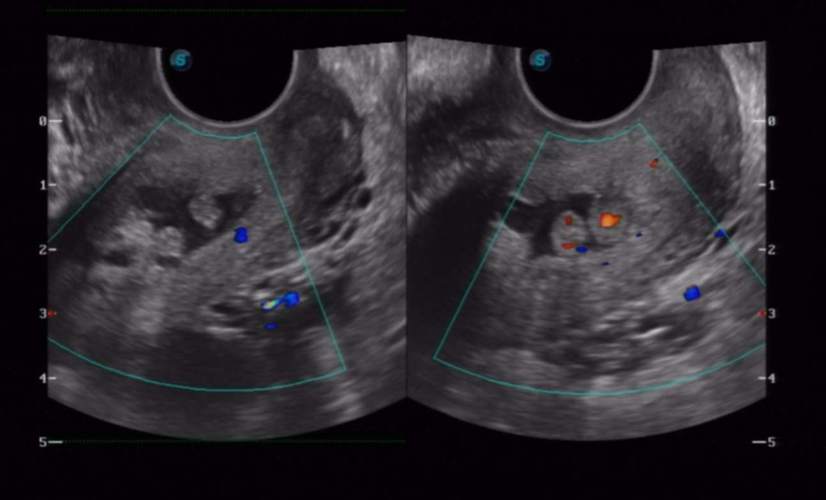

- 医生也可能会建议做B超检查,以排除其他引起出血的原因,并观察息肉的位置和大小。